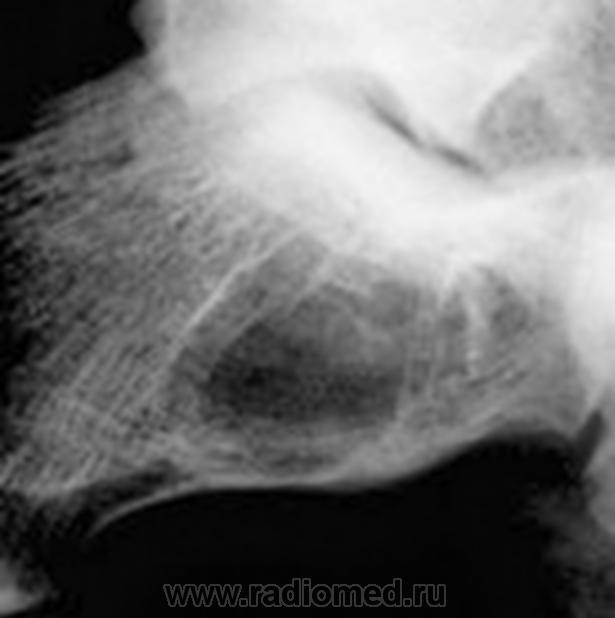

жалобы на незначительные боли в области левой пятки. несколко меяцев назад была травма,после которой полявиась припухлость в области пятки.К врачу не обращался. После мед осмотра в школе направлен на рентгенографию.

Навскидку - костная киста.

Спасибо за быстрый ответ. Я тоже о ней подумала.Но радом еще мелкие полостюшки.

1- псевдокиста пяточной кости, данная локализация характерная, но клинику она обычно не даёт а если и дает то редко, я уже выкладывал случай:

2-остеомиелит, возможно посттравматический;

3- менее вероятно доброкачестванная новообразование;